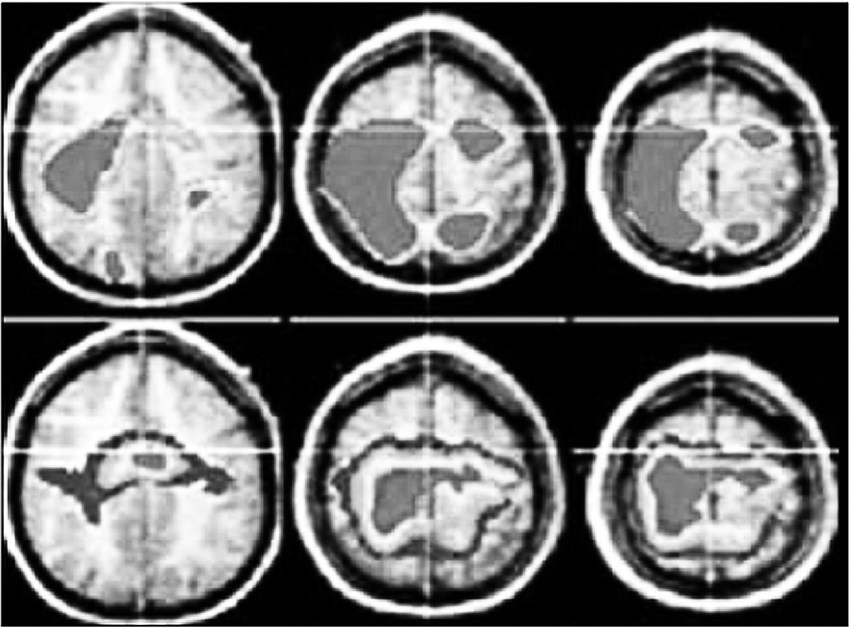

Функциональная магнитно-резонансная томография (ФМРТ) (рис. 3) позволяет измерить приток крови к различным частям мозга во время выполнения задач или воздействия стимулов. Используются детальные трехмерные изображения, сгенерированные компьютером на основе обнаруженных колебаний кровотока в ответ на нейронную активность.

Например, на рис. 4 представлены сканы мозга во время сна и бодрствования. Спящий мозг (три нижних рисунка) воспроизводит нейронную активность, напоминающую ту, что предшествовала сну во время бодрствования (три верхних рисунка).

Рис. 4. Функциональная магнитно-резонансная томография мозга во время сна и бодрствования [135]

Одно из достоинств ФМРТ – возможность исследовать глубокие структуры мозга, обеспечить возможность сравнительно продолжительного наблюдения активности мозга испытуемого во время действия конкретных стимулов или раздражителей. К недостаткам данного метода относится необходимость предельной неподвижности субъекта исследования, связанная с дискомфортом для испытуемых.